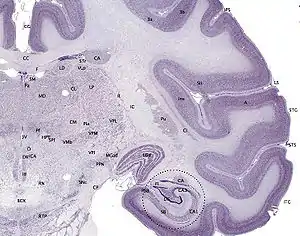

The hippocampus, including the dentate gyrus, has the shape of a curved tube, which has been compared to a seahorse, and to a horn of a ram, which after the ancient Egyptian god often portrayed as such takes the name cornu Ammonis. Its abbreviation CA is used in naming the hippocampal subfields CA1, CA2, CA3, and CA4.[20] It can be distinguished as an area where the cortex narrows into a single layer of densely packed pyramidal neurons, which curl into a tight U shape. One edge of the "U," – CA4, is embedded into the backward-facing, flexed dentate gyrus. The hippocampus is described as having an anterior and posterior part (in primates) or a ventral and dorsal part in other animals. Both parts are of similar composition but belong to different neural circuits.[22] In the rat, the two hippocampi resemble a pair of bananas, joined at the stems by the commissure of fornix (also called the hippocampal commissure). In primates, the part of the hippocampus at the bottom, near the base of the temporal lobe, is much broader than the part at the top. This means that in cross-section the hippocampus can show a number of different shapes, depending on the angle and location of the cut.

In a cross-section of the hippocampus, including the dentate gyrus, several layers will be shown. The dentate gyrus has three layers of cells (or four if the hilus is included). The layers are from the outer in – the molecular layer, the inner molecular layer, the granular layer, and the hilus. The CA3 in the hippocampus proper has the following cell layers known as strata: lacunosum-moleculare, radiatum, lucidum, pyramidal, and oriens. CA2 and CA1 also have these layers except the lucidum stratum.[23][24]

The major input to the hippocampus is through the entorhinal cortex (EC), whereas its major output is via CA1 to the subiculum.[26] Information reaches CA1 via two main pathways, direct and indirect. Axons from the EC that originate in layer III are the origin of the direct perforant pathway and form synapses on the very distal apical dendrites of CA1 neurons. Conversely, axons originating from layer II are the origin of the indirect pathway, and information reaches CA1 via the trisynaptic circuit. In the initial part of this pathway, the axons project through the perforant pathway to the granule cells of the dentate gyrus (first synapse). From then, the information follows via the mossy fibres to CA3 (second synapse). From there, CA3 axons called Schaffer collaterals leave the deep part of the cell body and loop up to the apical dendrites and then extend to CA1 (third synapse).[26] Axons from CA1 then project back to the entorhinal cortex, completing the circuit.[27]